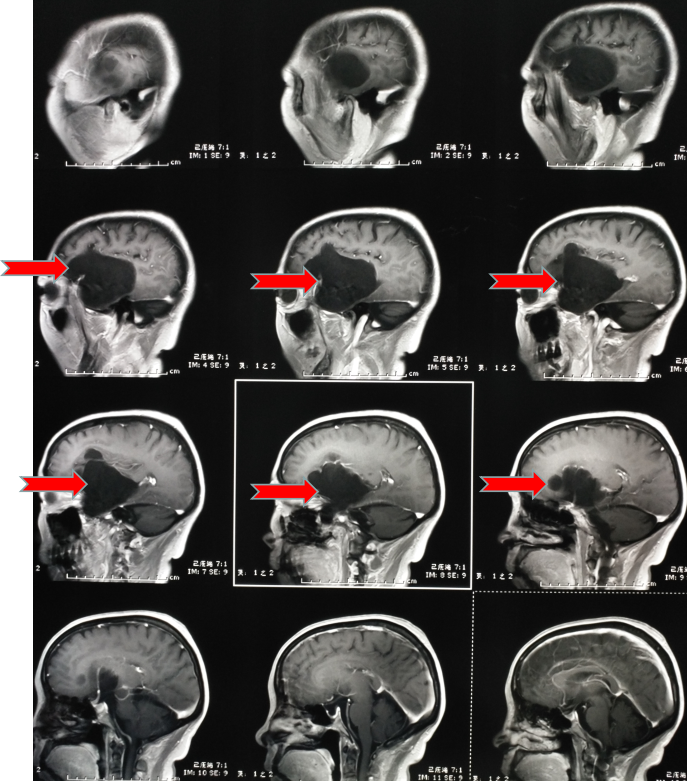

第二天趕緊到醫(yī)院看了一下,醫(yī)生說這是癲癇,隨后給她開了“丙戊酸鈉”長期口服,用藥后仍然每年有1-2次發(fā)作,大多是在晚上,有時(shí)即使沒有發(fā)生四肢抽搐,但有一種異樣的感覺。雖然這兩年很少發(fā)作了,但異樣感覺一直存在。今年她順利退休了,但教師的職業(yè)病——頸椎病卻讓他頸肩部以及上肢經(jīng)常麻木酸困,所以查了一下磁共振,確實(shí)存在頸椎病,但不需要手術(shù),只需保守治療即可。但意外的是發(fā)現(xiàn)了腦子里面長了個(gè)瘤子,大小約7厘米。

頭部磁共振提示腫瘤大小約7cm

一看片子,確認(rèn)是良性腫瘤,準(zhǔn)確點(diǎn)說應(yīng)該是一種叫做表皮樣囊腫的腫瘤,生長時(shí)間比較長,所以在早期很難發(fā)覺,經(jīng)常是在偶爾查頭部CT或者磁共振時(shí)發(fā)現(xiàn)。我給她說,這就是一直困擾她幾十年的病根所在,只要將它切除,她的癲癇和異樣感會(huì)逐漸消退,否則,隨著腫瘤增大,不僅會(huì)癲癇反復(fù)發(fā)作,而且會(huì)影響其他神經(jīng)功能??紤]再三,最終她還是選擇手術(shù)治療。